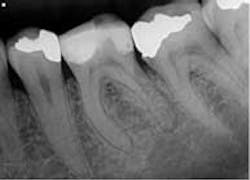

Clinical evaluation revealed no intraoral or extraoral swelling and a large composite restoration in tooth No. 19. Endodontic testing revealed severe pain to cold in tooth No. 19; all other tests were within normal limits (WNL). All other teeth in the quadrant tested WNL. The diagnosis was irreversible pulpitis with normal apical tissue. Radiographic exam revealed a large composite restoration and abnormal anatomy suggesting radix entomolaris. Radix entomolaris is a supernumerary root located distolingually in mandibular molars. The supernumerary root can also be found mesiobucally, and this is called radix paramolaris. The prevalence of a supernumerary root in mandibular molars has been found to be between 2.2% (Skidmore) and 21.5% (Yew and Chan). It is important to carefully study our preoperative and working radiographs in order to recognize the presence and location of abnormal anatomy.

The patient was given treatment options and informed consent, and elected to begin treatment immediately. Profound anesthesia was achieved using two carpules of 2% lidocaine for IANB and one carpule of Septocaine for long buccal infiltration. The tooth was isolated with a rubber dam and accessed under Global operating microscope using round burs and an Endo-Z bur. The distal canal was located in its typical orientation, centered buccolingually between the mesial canals. However, the canal leading to the radix entomolaris was found far to the lingual and off-center. Working length was determined using Root ZX II electronic apex locator. ISO size 6, 8, and 10 files were used to create initial glide path. Instrumentation was completed using ProGlider files to establish glide path, and a combination between Protaper and Vortex Blue files with full-strength sodium hypochlorite irrigation. QMix was placed into the canals after irrigation and agitated with EndoActivator to remove the smear layer and for its antibacterial properties. The canals were filled using warm vertical condensation with System B and Calamus backfill. The patient was given a six-month follow-up appointment and ibuprofen 600 mg for postoperative discomfort.